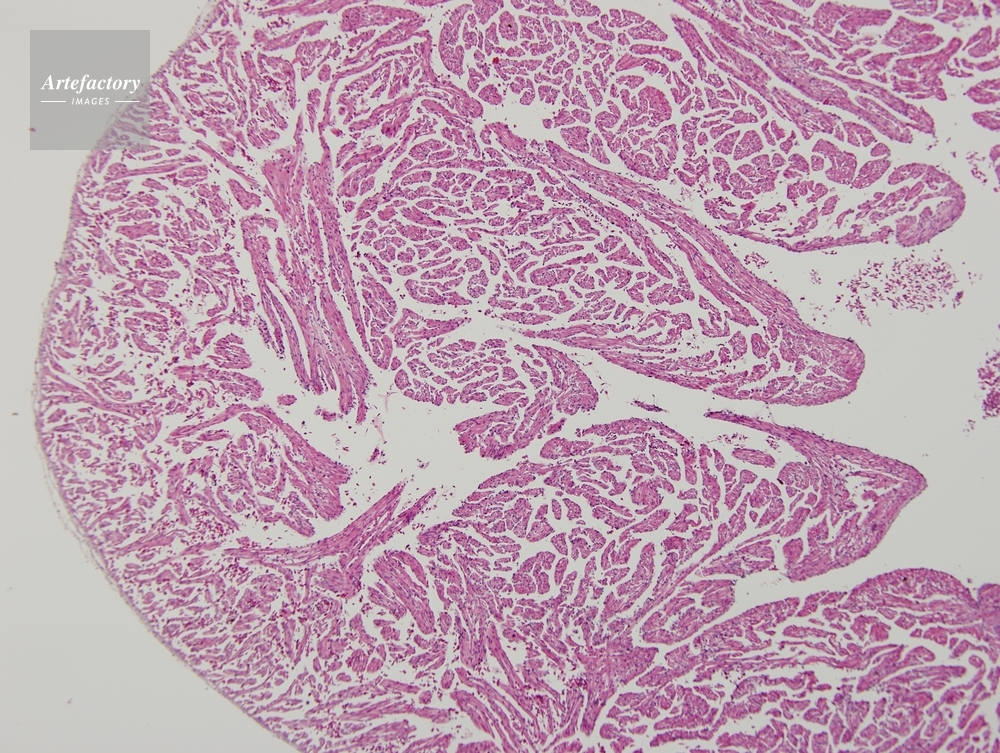

| 作品タイトル | ウシガエル,心臓 | モデルリリース | なし | |